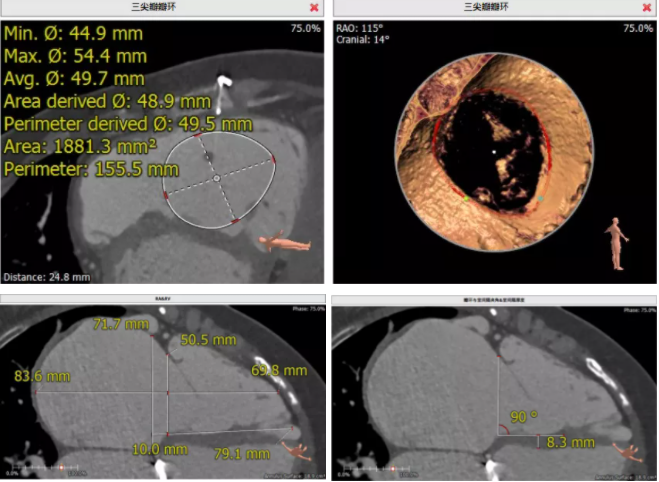

患者為68歲女性,14年前因“反復(fù)感冒、氣促”,檢查發(fā)現(xiàn)心臟瓣膜病,接受了“二尖瓣機(jī)械瓣置換術(shù)”。約5年前出現(xiàn)雙下肢水腫,活動(dòng)后心累氣緊,心臟彩超提示:三尖瓣返流。近年來三尖瓣返流逐漸加重并伴有輕微黃疸、雙下肢水腫,雖長(zhǎng)期服用利尿劑治療,但效果欠佳。郭惠明教授團(tuán)隊(duì)結(jié)合病史、超聲及CT評(píng)估,考慮患者瓣膜置換術(shù)后,三尖瓣重度返流,再次開胸行體外循環(huán)手術(shù)風(fēng)險(xiǎn)高,經(jīng)團(tuán)隊(duì)整體評(píng)估,決定采用最適合患者的LuX-Valve三尖瓣置換系統(tǒng)行微創(chuàng)治療,根據(jù)測(cè)量結(jié)果選擇植入JS/TTVI-28-55型號(hào)的LuX-Valve瓣膜。

手術(shù)過程